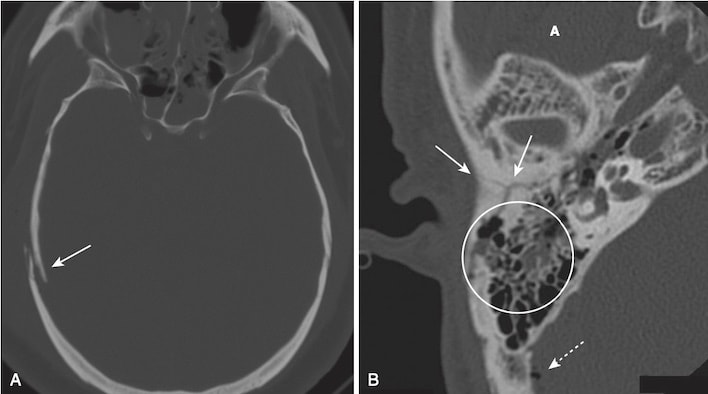

Gãy xương nền sọ (Basilar skull fractures)

- Gãy nền sọ là loại gãy nặng nề nhất và bao gồm một vết gãy thẳng ở đáy hộp sọ. Gãy xương có thể kèm theo các vết rách màng cứng làm rò rỉ dịch não tủy, có thể dẫn đến chảy dịch não tủy ở lỗ mũi hoặc lỗ tai.

- Có thể nghi ngờ gãy xương này nếu có không khí trong não (não chứa khí do chấn thương), chất dịch trong xoang chũm, hoặc mức dịch – khí trong xoang bướm (sphenoid sinus) (xem Hình 6, B).

- Gãy xương ổ mắt thường gặp nhất là gãy bung ra/bùng vỡ (blow-out fracture) (Hình 7), được tạo ra do tác động trực tiếp lên ổ mắt (ví dụ, một quả bóng chày đập vào mắt) và gây ra sự gia tăng đột ngột áp lực trong ổ mắt dẫn đến gãy của sàn ổ mắt dưới (vào trong xoang hàm trên/maxillary sinus) hoặc thành trong của ổ mắt (vào trong xoang sàng/ethmoid sinus). Đôi khi cơ thẳng dưới có thể bị kẹt trong chỗ gãy, dẫn đến hạn chế nhìn lên trên và nhìn đôi.

- Nhận biết gãy bung ra ổ mắt (xem Hình 7, A):

- Khí thũng ổ mắt. Không khí trong ổ mắt thông với một trong các xoang chứa không khí lân cận, hoặc xoang sàng hoặc xoang hàm trên

- Gãy xương qua thành trong hoặc sàn của ổ mắt

- Kẹt mỡ và / hoặc cơ ngoại nhãn, đi xuống dưới như khối mô mềm vào đỉnh xoang hàm trên

- Dịch (máu) trong xoang hàm trên

- Gãy ba chân (tripod fracture), thường là do tác động lực mạnh lên gò má, là một dạng gãy xương mặt tương đối phổ biến khác. Loại gãy liên quan đến việc tách gò má (zygoma) khỏi phần còn lại của mặt bằng cách tách đường khớp trán-gò má, gãy sàn ổ mắt và gãy thành ngoài của bên của xoang hàm trên cùng bên (xem Hình 7, B)